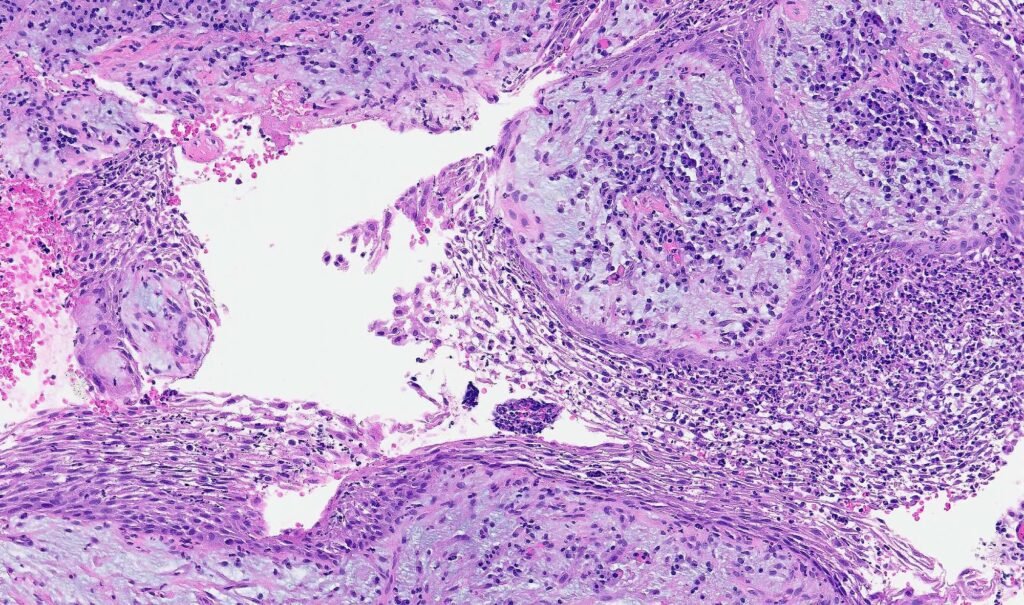

Anatomo-pathologie

Macroscopiquement :

- Masse charnue sphérique, de petit volume (tête d’épingle à 5 mm)

- Lisse, arrondie ou polylobée, de couleur rouge foncé

Microscopiquement — 4 zones concentriques :

| Zone | Nom | Contenu |

|---|---|---|

| I | Nécrose | Pus, contenu canalaire nécrotique, leucocytes polynucléaires, bactéries possibles |

| II | Contamination | Exsudative, leucocytes entourés de lymphocytes. Toxines actives, bactéries absentes |

| III | Irritation / Granulomateuse | Lymphocytes, plasmocytes, macrophages — zone de défense. Absence de microorganismes |

| IV | Stimulation | Encapsulation fibreuse, stimulation des fibroblastes et ostéoblastes |

Microscopiquement — 3 couches de la paroi kystique :

| Couche | Description |

|---|---|

| Interne | Épithélium pavimenteux stratifié, nombreux leucocytes |

| Moyenne | Tissu conjonctif jeune, éléments épithéliaux, mononucléaires |

| Externe | Tissu conjonctif pauvre en cellules, riche en fibres de collagène |

Aspect histologique

- Région de suppuration active, entourée de polynucléaires et quelques lymphocytes

- Trajet fistuleux bordé de tissu de granulation ou d’épithélium pavimenteux stratifié